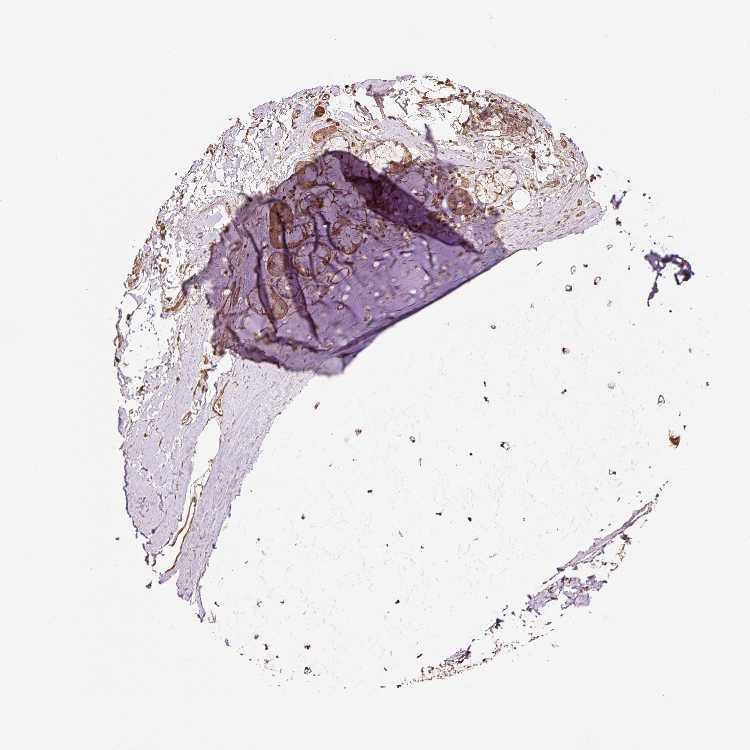

ADIPOSE TISSUE - Antibody stainingi

Antibody staining in the annotated cell types in the current human tissue is reported as not detected, low, medium, or high, based on conventional immunohistochemistry profiling in selected tissues. This score is based on the combination of the staining intensity and fraction of stained cells.

Each image is clickable and will lead to virtual microscopy that enables deeper exploration of all samples and also displays staining intensity scores, fraction scores and subcellular localization as well as patient and tissue information for each sample.

Antibody HPA037511Antibody CAB011686

Adipocytes Not detectedNot detected